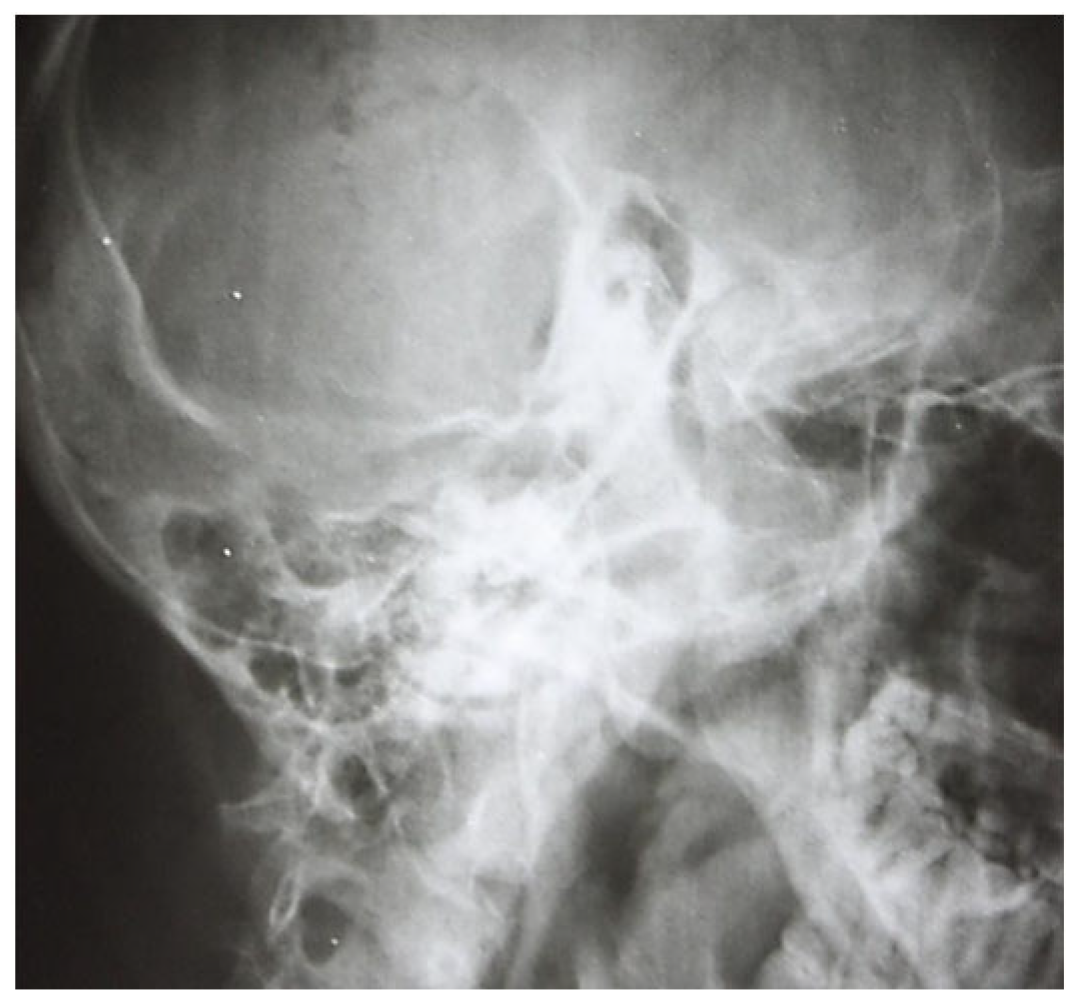

3.1.1. Conventional Radiology

3.1.2. Computed Tomography and Magnetic Resonance Imaging